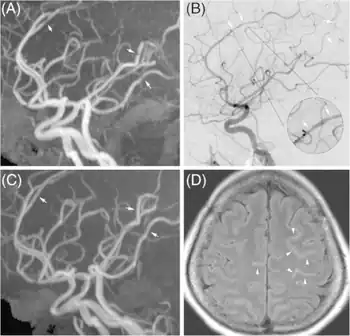

![]() | |

| Significant beading of all intracranial arteries, best demonstrated in the anterior cerebral arties due to RCVS. | |